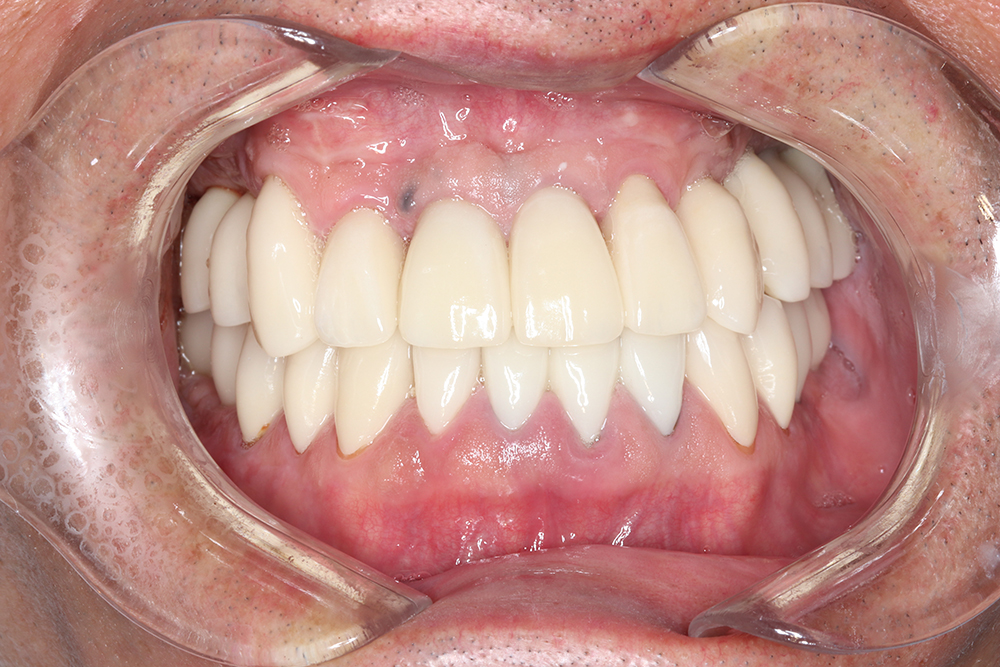

55歳 男性

- 主訴

- 前歯でしか咬めなく、食事を採るのに非常に困難で辛い

- 処置内容

- 上顎6本、下顎3本

- 治療費用

- 上顎:約230万(税込)下顎:約120万(税込)

- 治療期間

- 上顎:1年(仮歯まで8か月)下顎:8か月(仮歯まで5か月)

- リスク

- 上部構造物、仮歯の破折、術後の腫れ(3日)、人工歯根脱落リスクがあります